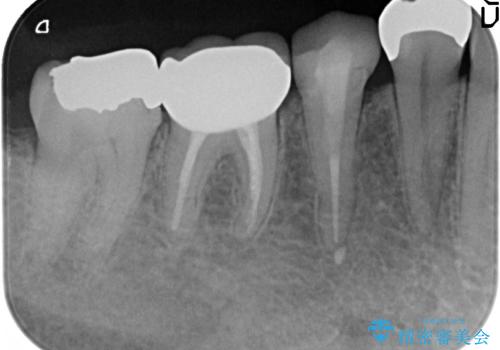

- 右下奥の歯茎がたまに腫れて膿が出るので診て欲しいといらっしゃった方の症例です。

診査の結果右下6の歯の神経が死んでいたため根管治療を行い、オールセラミッククラウンによる補綴を行いました。

今回用いたオールセラミッククラウンはジルコニアフレームという白い素材の上にセラミックを盛っているため、審美性が非常に高いのが特徴です。

また、ジルコニアは人工ダイヤモンドの材料にも使われているほど高い強度を持っており、そのためオールセラミッククラウンは審美性だけでなく、奥歯やブリッジの補綴も可能とするクラウンです。